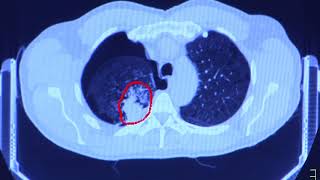

Prevention and screening programs include skin cancer, cervical cancer, breast cancer, lung cancer, colorectal cancer and prostate cancer.

There are variety of effective treatment options for cancer, all of which are tailored to the individual. The method of treatment depends on factors such overall patient health, age, type of cancer, its location and more.

Roper St. Francis Cancer Care’s highly-trained specialists are armed with the most advanced cancer-fighting tools available including robotically-assisted surgery, advanced radiation tools, clinical trials, chemotherapy and other infusion services.